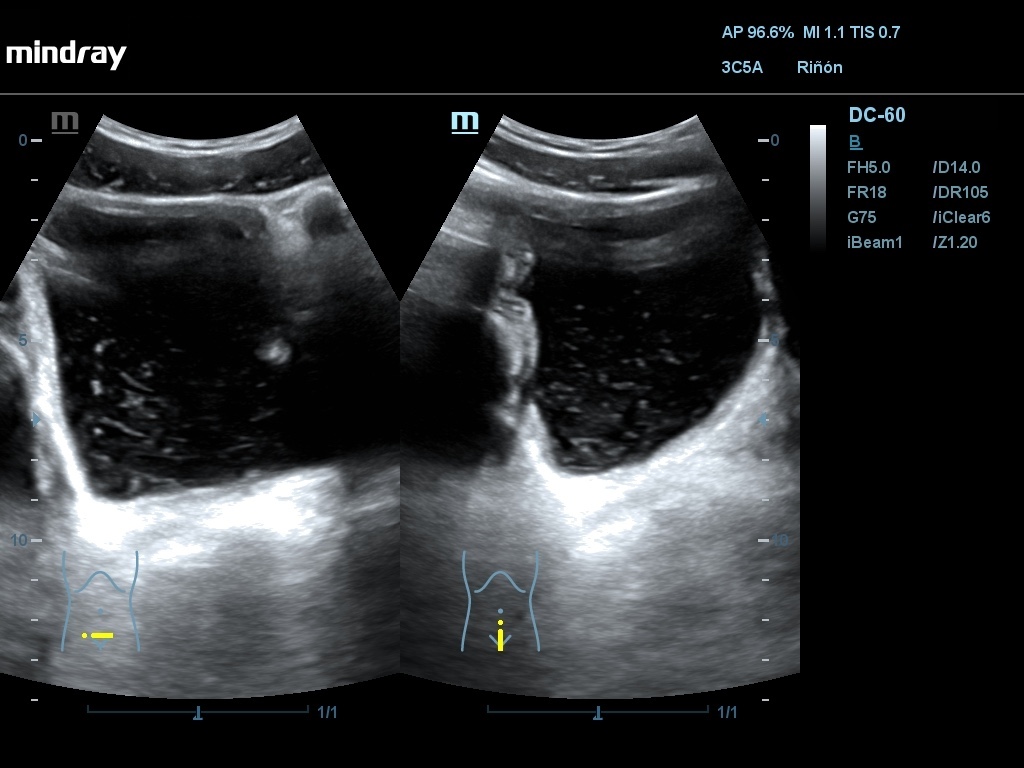

Ecografía: Se han observado varias imágenes poco habituales en vejiga urinaria: imágenes hiperecogénicas flotantes sin sombra posterior, móviles (detritus), engrosamiento de pared vesical que simula una vejiga no distendida con áreas anecoicas, pared con imagen en doble carril, masa vesical.

La sospecha inicial por criterios epidemiológicos es esquistosomiasis con afectación de vejiga urinaria. El diagnóstico diferencial se debe hacer con otras infecciones y tumores (raros en esta edad). En uno de los casos, AE considera que las imágenes se deben a vejiga poco replecionada y no las valora como patológicas. La masa vesical podría ser de tipo inflamatorio o tumoral.